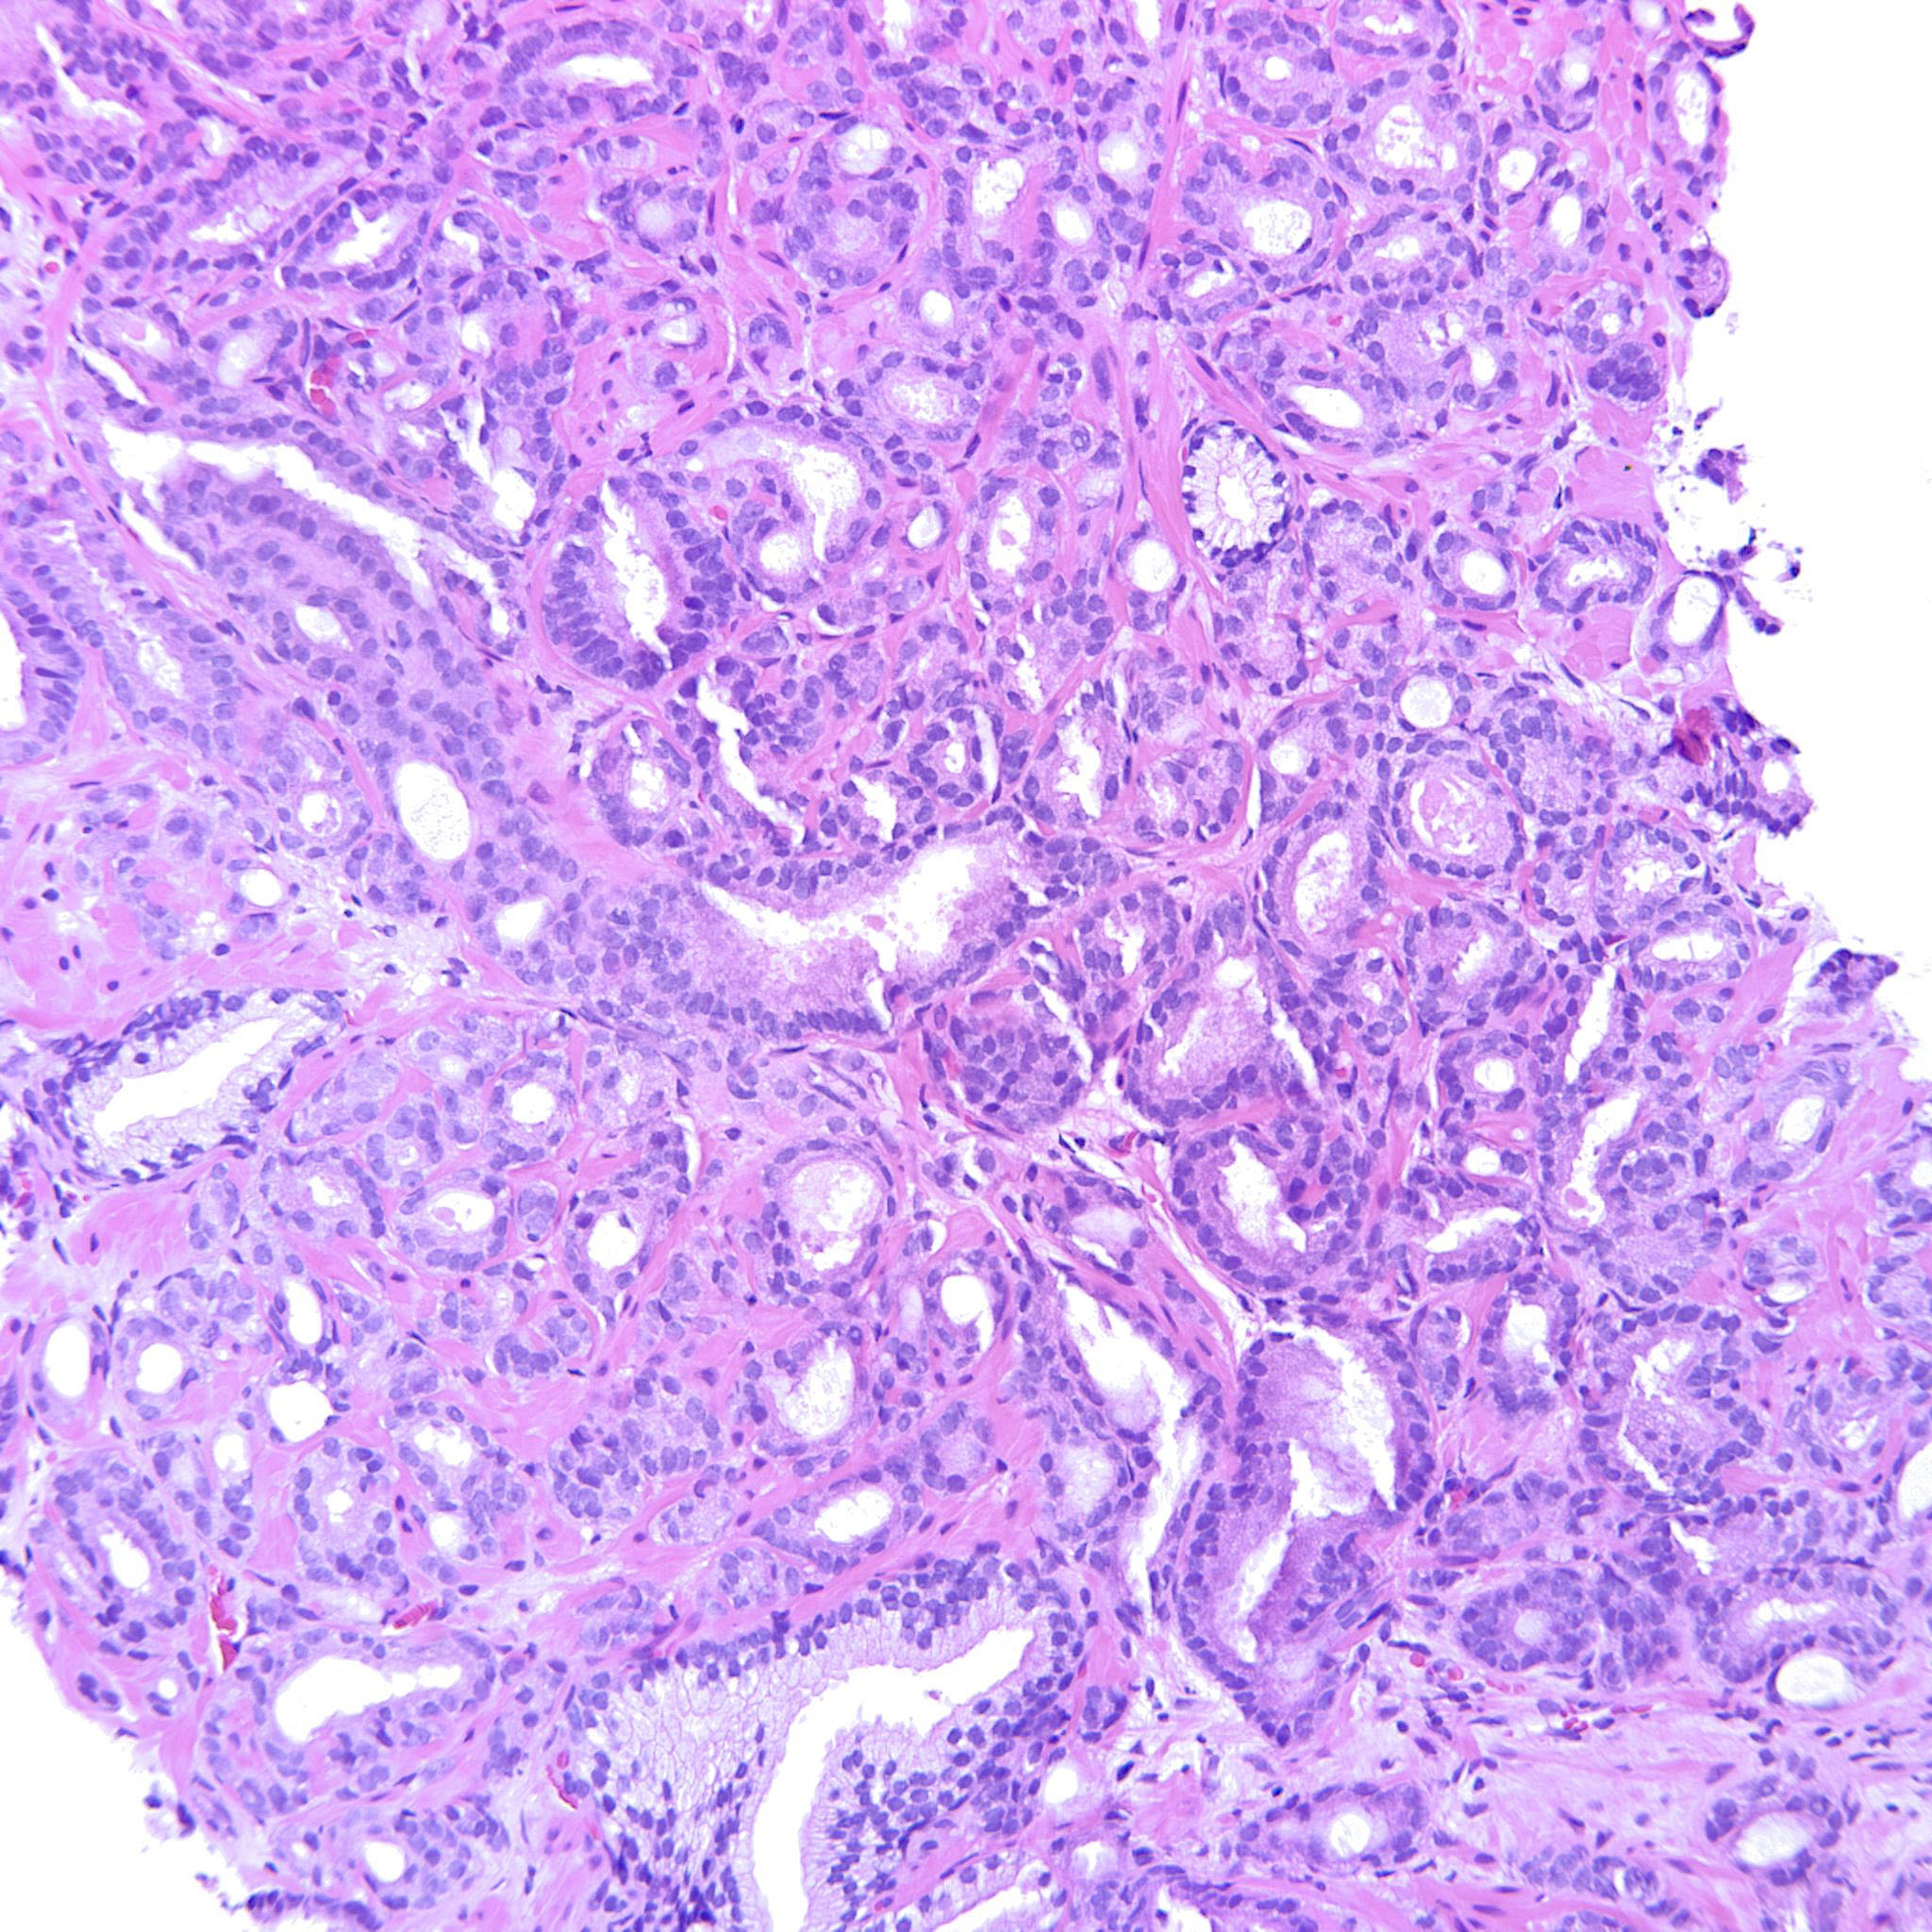

Prostate cancer grading

Case ID: 214